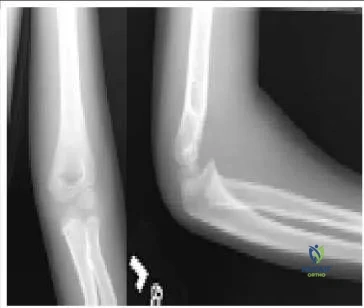

The radiographs (Slide) indicate which of the following diagnoses:

Correct Answer: Supracondylar humeral fracture

The radiographs indicate a supracondylar fracture of the distal humerus. The anterior humeral line should bisect the capitellum on the lateral view. The anterior and posterior fat pads are elevated. The fracture line may be seen on the anteroposterior and the lateral radiographs, although it is subtle. The cortical break of the coronoid fossa is evident. Surgeons must recognize

these fractures so that the patient and family may be given proper activity restrictions and expectations for improvement.